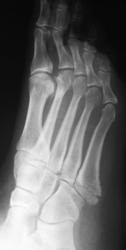

Травма.  Пациент направлен на рентгенографию стопы.

Может и в одиночестве, но ногу подвернул здорово. А перелом-то классический.

А мне не понравилась головка 2 плюсневой кости - уплощена, без видимых признаков перелома. Похоже на последствие остеохондропатии Келера?